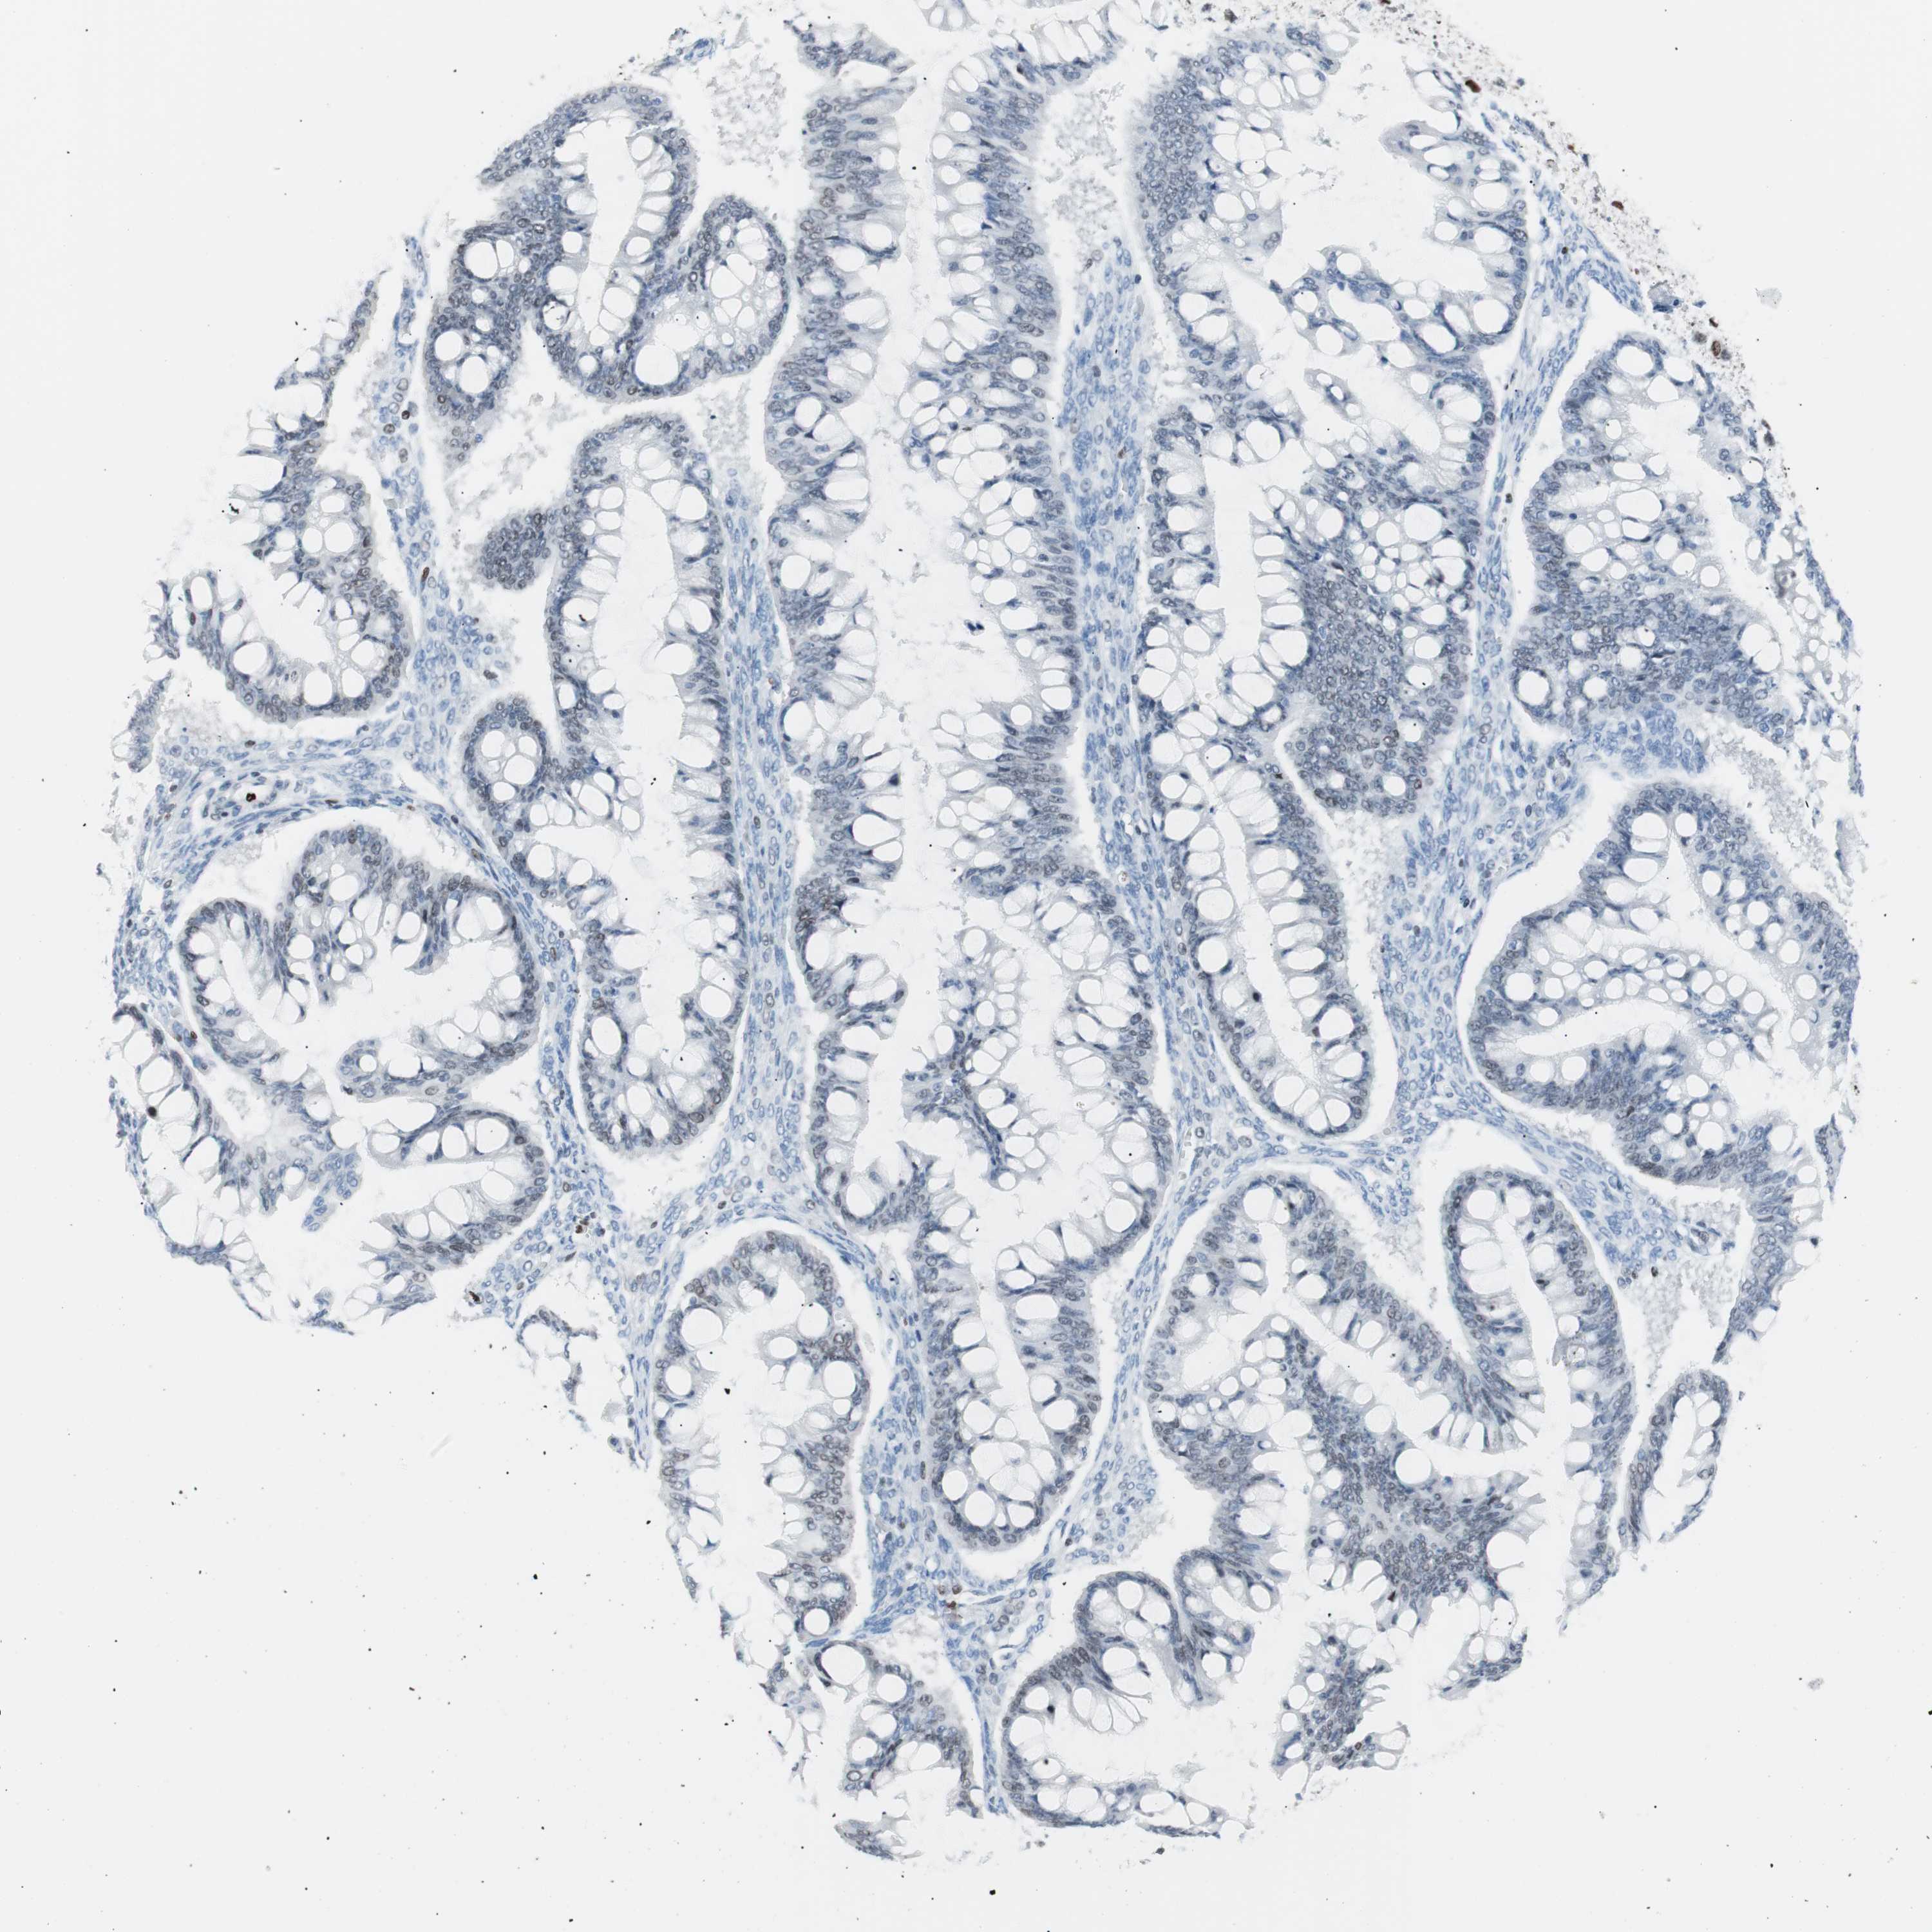

OVARIAN CANCER - Protein expressioni

A mouse-over function shows sample information and annotation data. Click on an image to view it in a full screen mode. Samples can be filtered based on level of antibody staining by selecting one or several of the following categories: high, medium, low and not detected. The assay and annotation is described here.

Note that samples used for immunohistochemistry by the Human Protein Atlas do not correspond to samples in the TCGA dataset.

Antibody stainingi

Antibody staining in the annotated cell types in the current human tissue is reported as not detected, low, medium, or high, based on conventional immunohistochemistry profiling in selected tissues. This score is based on the combination of the staining intensity and fraction of stained cells.

Each image is clickable and will lead to virtual microscopy that enables deeper exploration of all samples and also displays staining intensity scores, fraction scores and subcellular localization as well as patient and tissue information for each sample.

Antibody CAB004213

Cystadenocarcinoma, serous, NOS

Carcinoma, endometroid

Carcinoma, NOS

Cystadenocarcinoma, mucinous, NOS